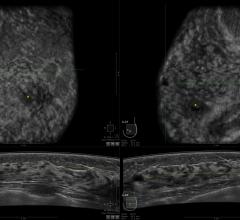

Women's health related to breast imaging, including mammography, breast MRI, ABUS, automated breast ultrasound, breast ultrasound, breast biopsy, PEM and positron emission mammography.

Despite decades of progress in breast imaging, one challenge continues to test even the most skilled radiologists ...

It has been nearly eight years since the world’s first digital breast tomosynthesis (DBT) mammography technology was ...

Artificial Intelligence (AI) is becoming more common place in radiology practices, and emerging technologies are ...